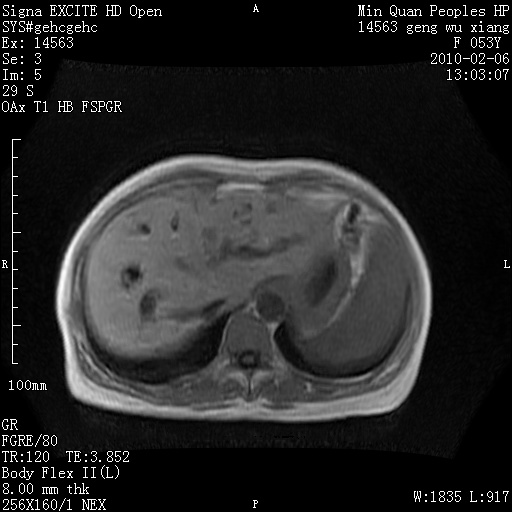

标题: MRI2762:胆道梗阻原因?

f,53y,全身黄染多日。

高位胆道梗阻 胆管癌可能性大

支持 高位胆道梗阻 胆管癌可能性大。